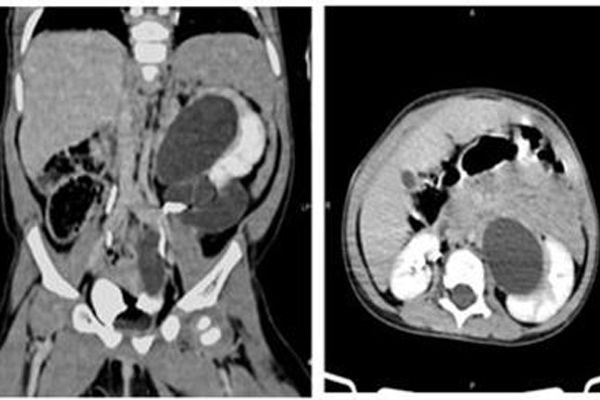

Hình ảnh 3 quả thận nhìn rõ sau khi chụp cắt lớp vi tính

BS Triệu Mạnh Toàn, Phó khoa Ngoại nhi tổng hợp cho biết, bệnh nhi bị giãn đài bể thận trái, có 2 thận trái với 2 hệ thống đài bể thận và niệu quản riêng biệt, đơn vị thận phụ bên trái (đơn vị thận trên) ứ nước do sa lồi niệu quản vào lòng bàng quang, còn chức năng. Thận dưới trái hình thái và chức năng bình thường.